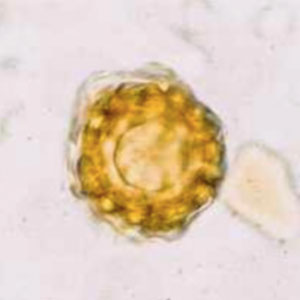

Ascaris eggs are oval and most often have an irregular outer surface (Petithory et al., 1995). Two forms of the parasite can be found:

- Fecundated eggs: they measure 45 to 75 µm in diameter and contain a non-vermiform embryo of varying density which occupies almost all the egg’s surface. One or more blastomeres can also be present according to the state of maturation of the egg. This form of egg often lacks at least part of its outer membrane (Petithory et al., 1995).

Spores can be mistaken with Ascaris eggs, namely downy mildew spores (Peronospora pisi). However, these spores are smaller in size (around 40 µm) and have a thicker outer sheath (Petithory et al., 1995).

Pollens can also be mistaken with Ascaris eggs

- Sage pollen seeds (Salvia sclarea): these pollen seeds measure between 40 and 50 µm in diameter. However, their outer membrane is thinner than the one of Ascaris eggs (Petithory et al., 1995).

- Basil pollen seeds (Ocimum basilicum): these pollen seeds measure between 60 and 65 µm in diameter. However, their outer membrane is green and more irregular than the one of Ascaris eggs (Petithory et al., 1995).

- Safflower pollen seeds (Carthamus tincorius): these are round pollen seeds of 55 to 60 µm in diameter, with an irregular outer membranes and small spicules. However, they are normally greener and more refringent than Ascaris eggs (Petithory et al., 1995);